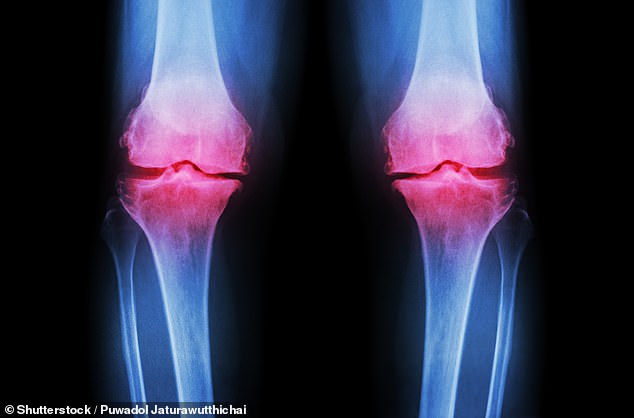

Osteoarthritis, which affects over 10 million people in the UK alone, occurs when cartilage at the ends of bones deteriorates. This leads to joint stiffness, chronic pain, and reduced mobility. Current management strategies often involve painkillers with potential side effects or lengthy physiotherapy regimens that many patients find difficult to sustain.